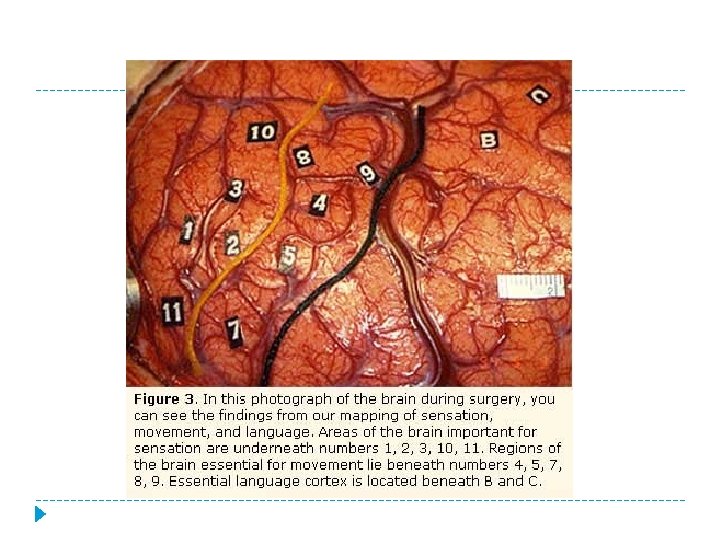

Watching the Brain “light up” Neurologists and scientists who specialize in studying the brain can take pictures of the brain of a person who is involved in various activities. “Brain mapping” attempts to relate the brain's structure to its function, or finding what parts give us certain abilities. (Nasr, Susan. “How the Brain Works”)

� Brain Mapping is unique and important because. . . …it shows what part of the brain is active during certain activities or thought processes.